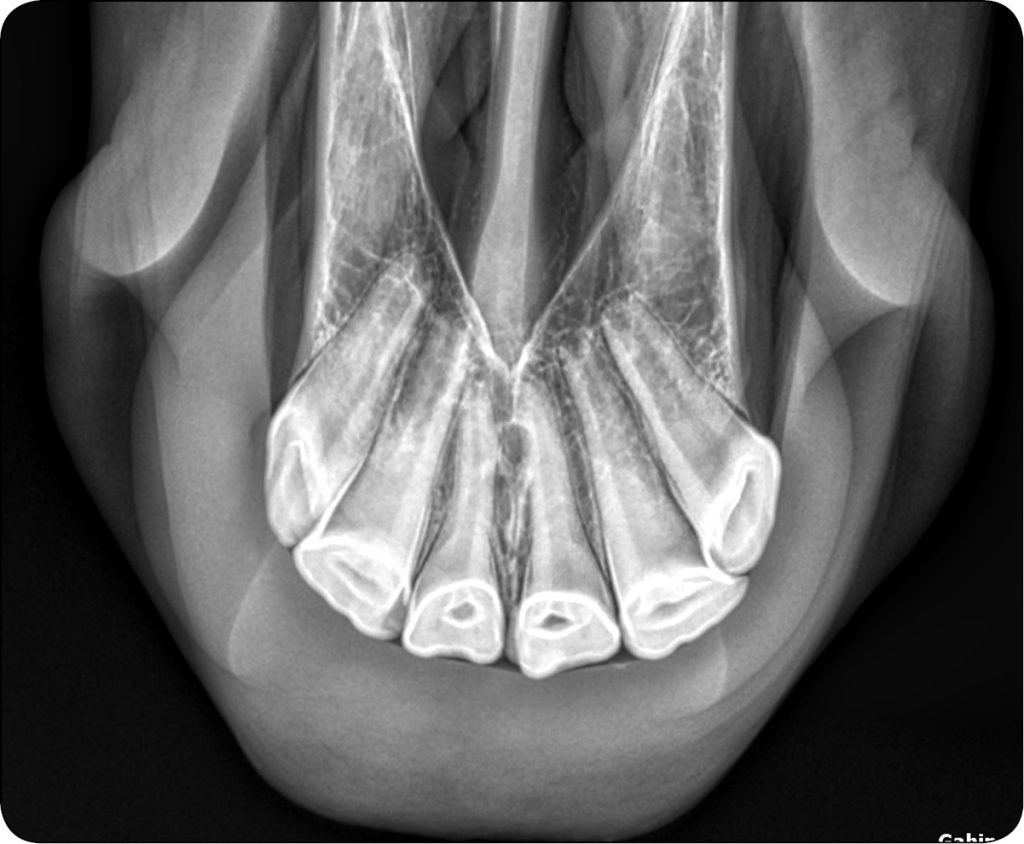

W celu wykonania zdjęć rentgenowskich siekaczy szczęki należy ustabilizować głowę zwierzęcia, następnie umieszcza się kasetę skierowaną dogrzbietowo, maksymalnie doogonowo w jamie ustnej (ryc. 5 i 6).

Ze względu na zmieniający się wraz z wiekiem kąt siekaczowy w zależności od pacjenta promienie rentgenowskie powinno się kierować pod kątem 45° u zwierząt młodych i 70-80° u koni starszych w stosunku do kasety. W przypadku nałożenia się na siebie koron skrajnych zębów siecznych w obrazie RTG należy wykonać dodatkowe projekcje skośne, prawe i lewe pod kątem 10-15°, umieszczając lampę rentgenowską po tej samej stronie co dany ząb. Aby zobrazować korzenie kłów szczęki, należy się upewnić, że detektor znajduje się [...]